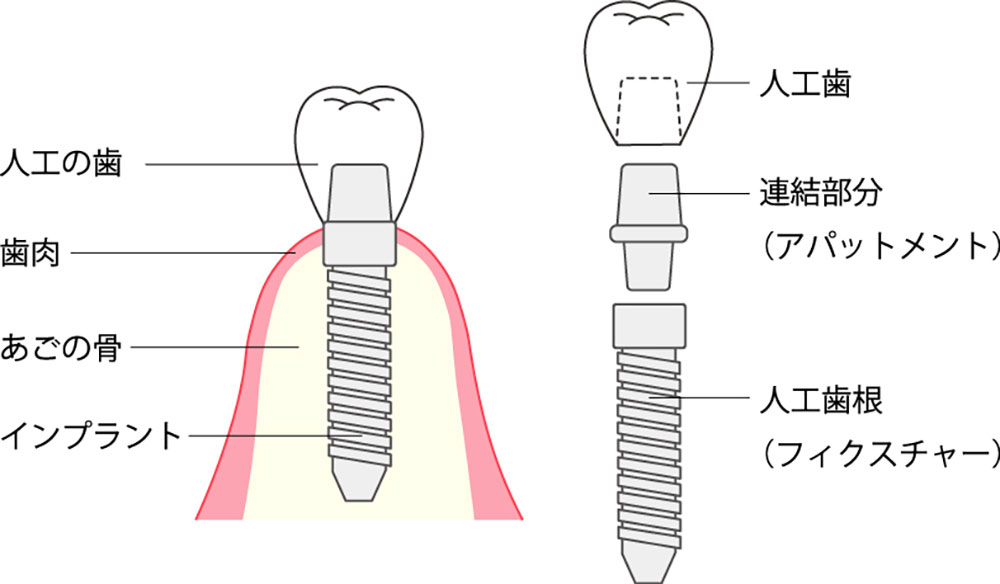

インプラントの構造

インプラントは、チタン製の人工歯根を顎の骨に埋め込み、その上に人工歯を装着することで、天然歯に近い見た目と咬み心地を再現します。大きく分けて3つのパーツで構成されています。

1.フィクスチャー(インプラント本体)

歯を失ってしまった箇所の顎の骨に埋め込む人工歯根部

2.アバットメント

フィクスチャーと上部構造をつなぐ連結部

3.上部構造

アバットメントに装着する人工歯の部分